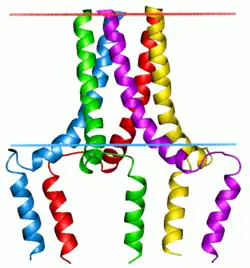

Phospholamban pentamer | |||||||||

Phospholamban, also known as PLN or PLB, is a micropeptide protein that in humans is encoded by the PLN gene.[5] Phospholamban is a 52-amino acid integral membrane protein that regulates the calcium (Ca2+) pump in cardiac muscle cells.[6]

This protein is found as a pentamer and is a major substrate for the cAMP-dependent protein kinase (PKA) in cardiac muscle. In the unphosphorylated state, phospholamban is an inhibitor of cardiac muscle sarcoplasmic reticulum Ca2+-ATPase (SERCA2)[7] which transports calcium from cytosol into the sarcoplasmic reticulum. When phosphorylated (by PKA) - disinhibition of Ca2+-ATPase of SR leads to faster Ca2+ uptake into the sarcoplasmic reticulum, thereby contributing to the lusitropic response elicited in heart by beta-agonists.[8] The protein is a key regulator of cardiac diastolic function. Mutations in this gene are a cause of inherited human dilated cardiomyopathy with refractory congestive heart failure.[9]